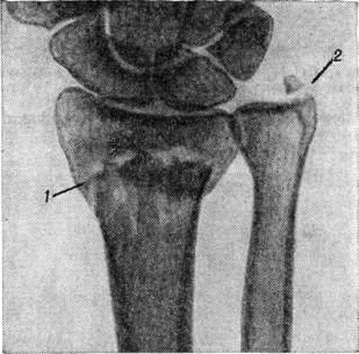

Основной рентгенологическое признак нарушения целости кости — линия Переломы Большое диагностическое значение имеет смещение отломков, наличие которого настолько бесспорно доказывает нарушение целости кости, что надобность в дифференциальной диагностике отпадает. Как бы подробно ни была описана рентгенологическое картина Переломы, наиболее полное и правильное представление о степени и характере смещения отломков врач может составить лишь при непосредственном просмотре снимков. Захождение отломков одного за другим при продольном смещении на рентгенограмме в одной проекции может сопровождаться наслоением теней концов отломков — так называемый суперпозицией теней. В этом случае точное определение смещения отломка возможно на основании данных снимков во второй проекции. При Переломы плоских костей (лопатка, ребра, таз и другие), при которых по техническим причинам производство снимка во второй проекции затруднено, суперпозиция отломков часто является единственным достоверным признаком Переломы Распознавание продольных смещений с расхождением отломков обычно не представляет каких либо затруднений. Подобного рода смещения наблюдаются при Переломы надколенника с разрывом связочного аппарата, локтевого отростка, вертелов бедра, отрывах костных выступов, к которым прикрепляются мышцы, сокращающиеся при повреждениях и приводящие к расхождению. Интерпозиция мягких тканей между отломками костей при рентгенологическое исследовании не распознается. Различные виды Переломы в наиболее информативных проекциях представлены на рисунок 4—11.